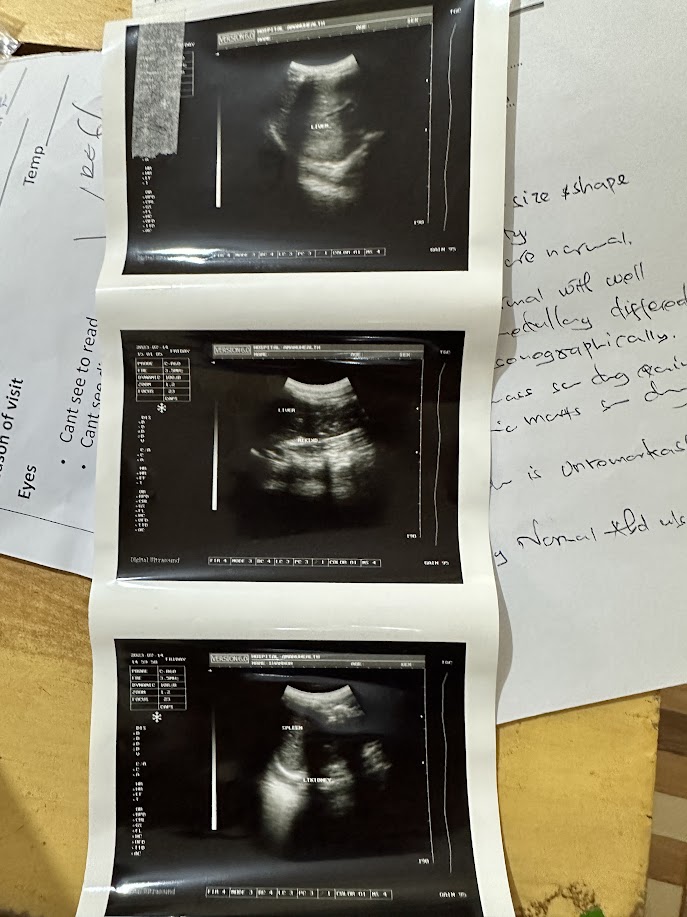

Our x ray technician did ultrasounds with our new machine. | | |